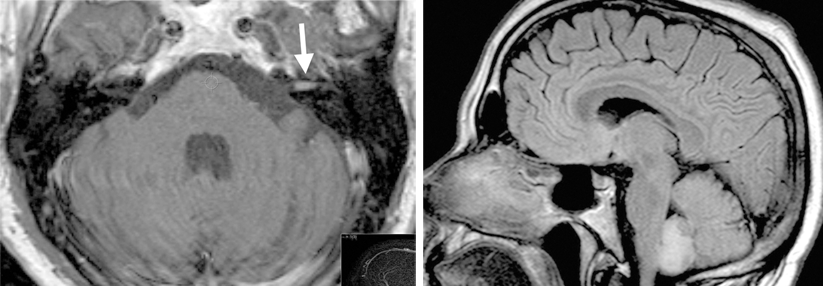

Schwindel gehört zu den Top Ten der Gründe für eine Vorstellung in der Hausarztpraxis, sagte Prof. Dr. Ertunc Altiok, Uniklinik RWTH Aachen. Die S3-Leitlinie definiert Schwindel als eine „Unsicherheit im Raum“, die auf verschiedene Organsysteme oder auch die Psyche zurückgehen kann. Die wesentliche Ersteinschätzung erfolgt durch die Anamnese, die Frage nach bestehender Medikation und eine körperliche Untersuchung.

Aufschlussreich sind die genaue Art und Dauer der Symptome. So ist ein Drehschwindel oft vestibulär (mit) verursacht. Eine Gangunsicherheit „bei klarem Kopf“ dagegen deutet z.B. auf eine Polyneuropathie hin, möglich ist aber auch eine bilaterale Vestibulopathie. Letztere kann auch…